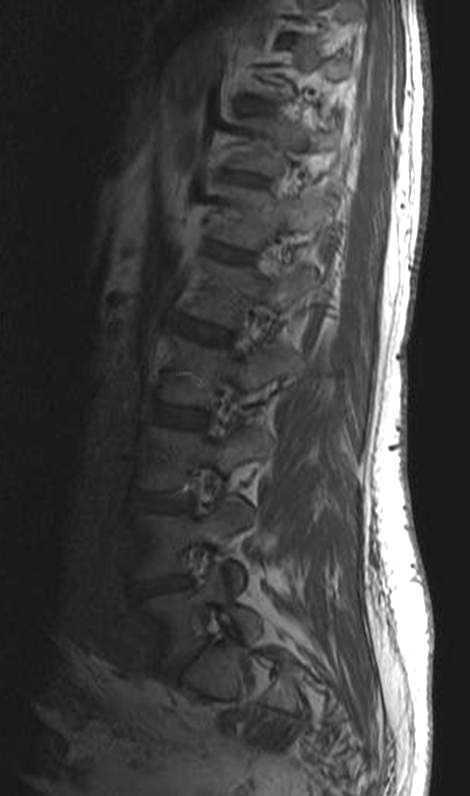

Se realizó una resonancia magnética (RM) de la columna lumbar (sin y tras contraste intravenoso) y se observaron, además de la masa retroperitoneal que comprimía la VCI, unas imágenes puntiformes y lineales hipointensas en todas las secuencias que ocupaban el espacio epidural adyacente al muro posterior de las vértebras lumbosacras, que se extendían a través de los agujeros de conjunción hacia las partes blandas perivertebrales (figs. 1-3). Esta alteración correspondía a estructuras vasculares dilatadas dependientes del plexo venoso epidural vertebral.

Fig. 3. Resonancia magnética tras contraste intravenoso: (A) sagital línea media y (B) axial. Se aprecia masa retroperitoneal (asterisco) y dilatación secundaria de las venas radiculares. Nótese la deformidad del saco tecal provocada por lipomatosis epidural (flechas).